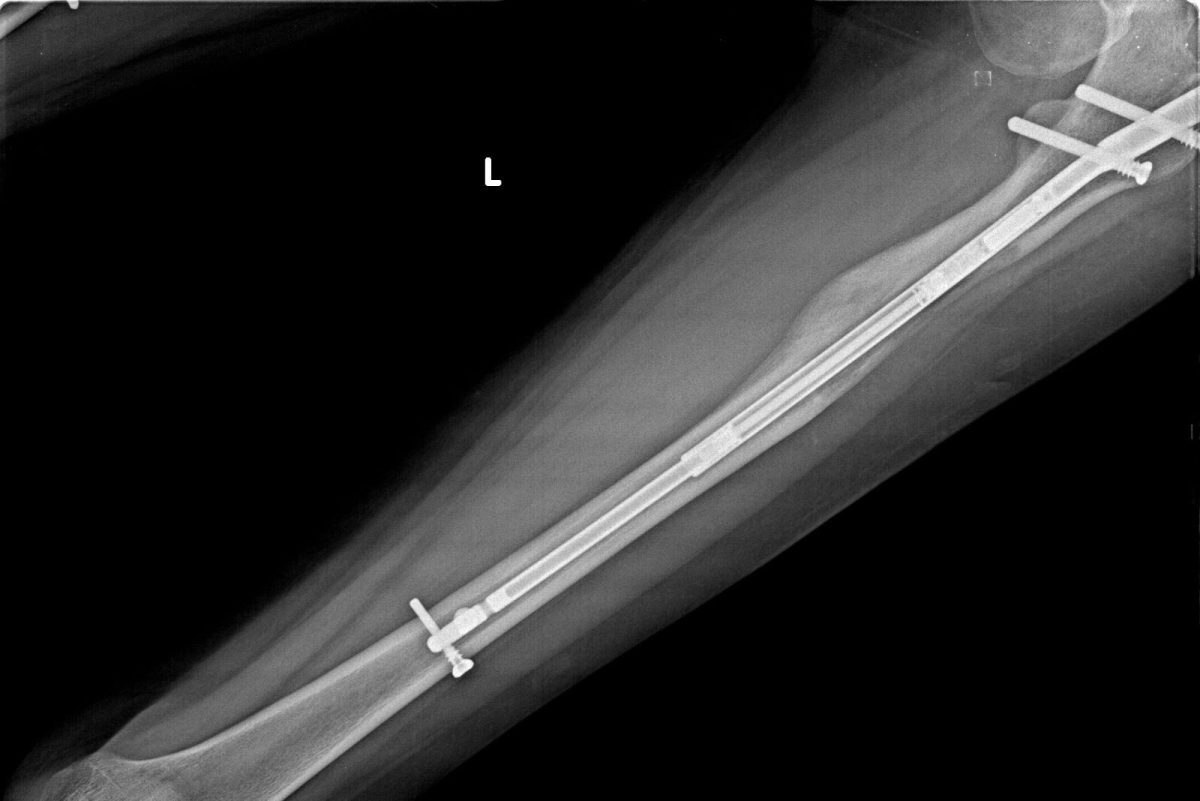

İntramedüller Çivi;

İntramedüller çivi veya çubuk, içerden sabitleme olarak kullanılır ve çelik alaşımından yapılır. Doktor, röntgen görüntülerini inceleyerek çivinin boyutuna karar verir. (8,5 mm, 10,7 mm, 11,5 mm or 12,5 mm) Ameliyat sırasında kemik boşluğuna cerrahi olarak gömülür.